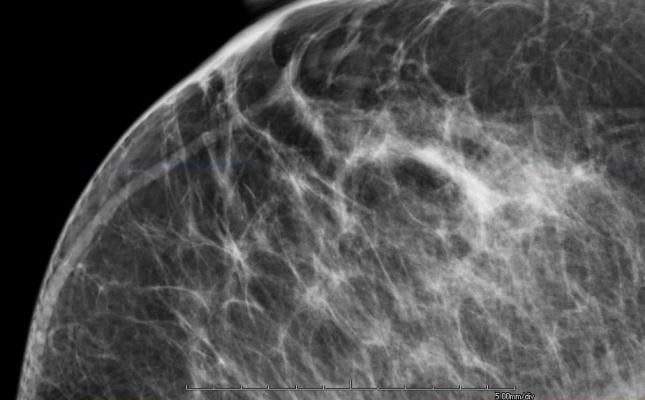

April 15, 2014 — VuComp Inc. announced it has released an updated version of its M-Vu Breast Density technology. The new M-Vu Breast Density 2.0 adds a critical dimension to the analysis of dense breast tissue. The VuComp density category, analogous to the BI-RADS breast density composition category, is now correlated to not only the amount, but also the distribution – the actual dispersion – of fibroglandular tissue.

M-Vu Breast Density automatically and rapidly assesses breast density and provides consistent and accurate measurements. The tool evaluates mammograms by analyzing the structure, texture and dispersion of the tissue, rather than simply estimating total fibroglandular volume. To ensure product effectiveness, the findings of a panel of 13 expert radiologists were used to calibrate the VuComp density categories to the American College of Radiology’s (ACR) Breast Imaging Reporting and Data System (BI-RADS) standard. The M-Vu algorithms quantify areas with a dense appearance that could hide cancer, and convert them to categories corresponding to the recently updated standard. This exclusive approach using appearance-based texture and dispersion analysis provides useful adjunctive information. M-Vu Breast Density is the only commercially available, U.S. Food and Drug Administration (FDA) -cleared system that employs this scientific methodology.

Clinical studies have shown that dense breasts can hide a cancerous lesion by reducing the ability to visualize fine structures and details that could indicate a malignant abnormality, making breast cancer detection in a mammogram more difficult. Patients with dense breast tissue may be recommended for additional screening exams. Legislation has passed in 16 states requiring physicians to notify patients if their breast density is in one of the two higher categories.